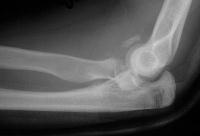

Injury:

Click for larger image